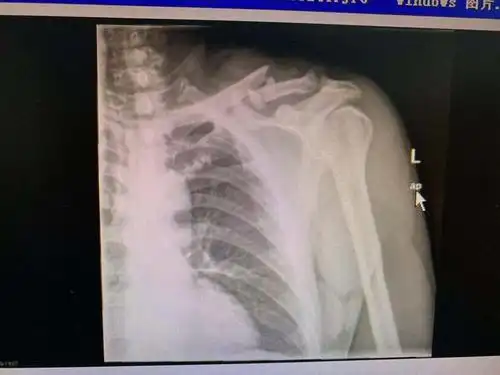

左锁骨粉碎性骨折